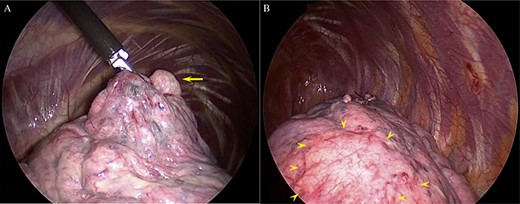

(A) The bullae causing pneumothorax (arrow) and (B) multiple telangiectasias under the visceral pleura (arrowhead).

recurrent intermittent epistaxis every few months and was monitored for PAVMs using computed tomography (CT) examinations every 6 months. He had a family history of HHT in his father and grandfather. After systemic examinations, he was diagnosed with HHT because he met the diagnostic criteria, including the presence of PAVM, recurrent epistaxis, and a family history of HHT, although genetic testing was not performed. A chest CT scan showed a left pneumothorax and apical bullae on both sides of the upper lobe (Fig. 1). In addition, a total of six PAVMs (four in the right lung, two in the left lung) were shown on the chest CT (Fig. 2). All PAVMs were located peripherally with the largest one being 3 mm in diameter. No AVM was detected in the brain or abdomen on CT. He was treated conservatively and then pneumothorax was improved. Six months later, the patient complained of cough and was diagnosed with pneumothorax by chest X-ray. To prevent the recurrence of the pneumothorax, the patient was offered video-assisted thoracic surgery. Intraoperatively, apical bullae and multiple telangiectasias were identified under the visceral pleura (Fig. 3). We performed wedge resection of the left upper lobe including the apical bullae. The postoperative histopathological findings of the resected specimen revealed pulmonary bullae (Fig. 4). The postoperative course was uneventful, and the patient was discharged on postoperative Day 2. He underwent catheter embolization for PAVMs in another hospital. His SpO2, which was measured before catheter embolization, was 97% on room air. There was no remarkable change in SpO2 after the intervention. No recurrence of the pneumothorax was observed during a 3-year follow-up.